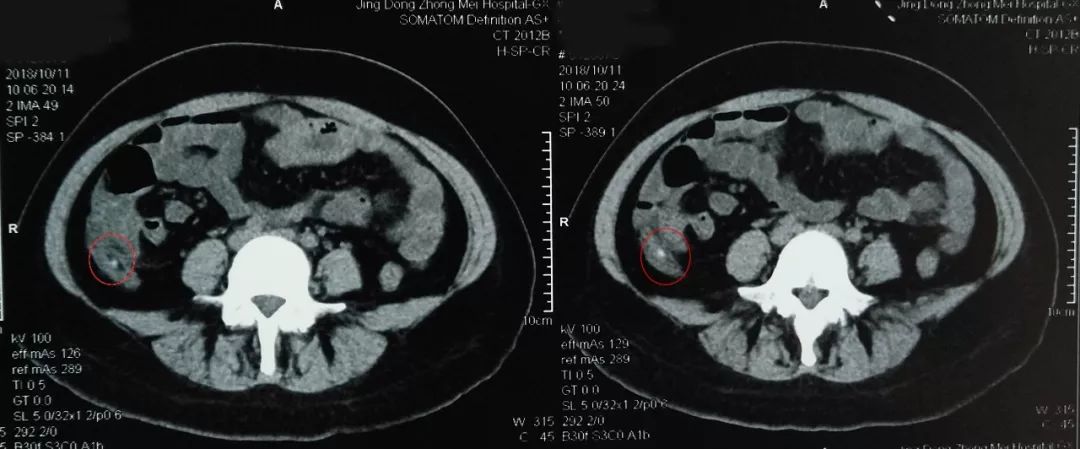

影像报告:CT检查结果报告阑尾粪石嵌顿

患者做好肠道准备后于30日上午在内镜室进行了内镜下逆行阑尾炎治疗术。电子结肠镜到达回盲部, 进入盲肠,可见:阑尾开口呈半月形,边缘粘膜充血、水肿,诊断考虑“急性阑尾炎”。随后,在斑马导丝引导下将取导管引导入阑尾腔用生理盐水进行阑尾腔反复冲洗可见乳白色脓液涌出,见脓液流尽用,并用替硝唑保留阑尾灌注,退镜,患者自诉腹痛明显缓解。